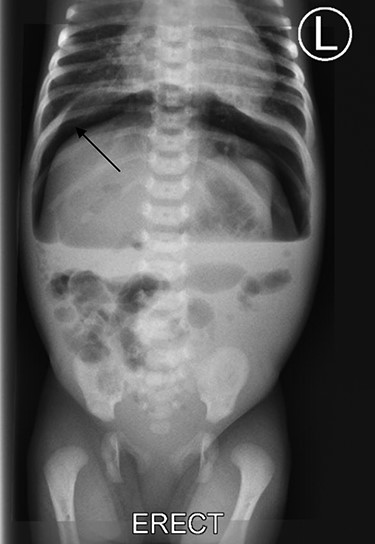

Provisional diagnosis of intestinal obstruction due to necrotizing enterocolitis with early neonatal sepsis was made. Initial blood investigations showed hemoglobin of 15.4 g/dl, BUN of 1.72 mmol/l and a serum creatinine of 72 μmol/l. Abdominal-pelvic ultrasound w revealed focal dilated bowel loops with poor peristalsis, free intraabdominal fluid. The liver, spleen and kidneys had normal echo-texture and impression of pneumoperitoneum was made. Plain abdominal X-ray showed features of pneumoperitoneum (Fig. 1).

Plain abdominal X-ray shows free air under right dome of diaphragm (arrow).

A wide range of clinical features can be presented in neonates, ranging from signs of septicemia to intestinal obstruction due to paralytic ileus from peritonitis from contamination [3, 8]. The authors diagnosed the pneumoperinoneum from a plain abdominal X-ray showing free gas under the right hemi-diaphragm as this was also the case in the index case. Other modalities can be considered like contrast studies where a leakage of the contrast can be seen into the peritoneum cavity which can aid in the diagnosis and point the site of perforation in the gastrointestinal tract [5].